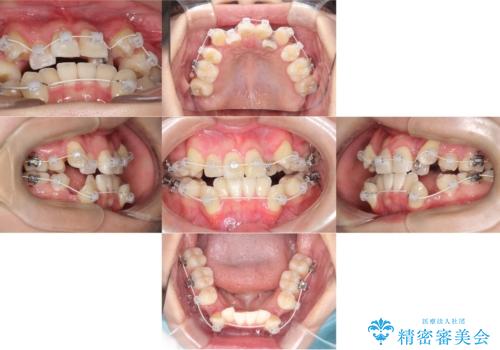

- 治療計画

- 「歯のでこぼこを治したい」を主訴に来院された患者様です。 上下ともに、歯のでこぼこが強く、上下左右4の抜歯をし、ワイヤー矯正で治療を行いました。

- ワイヤー(審美装置)

- 2年10ヶ月

- 30回以上